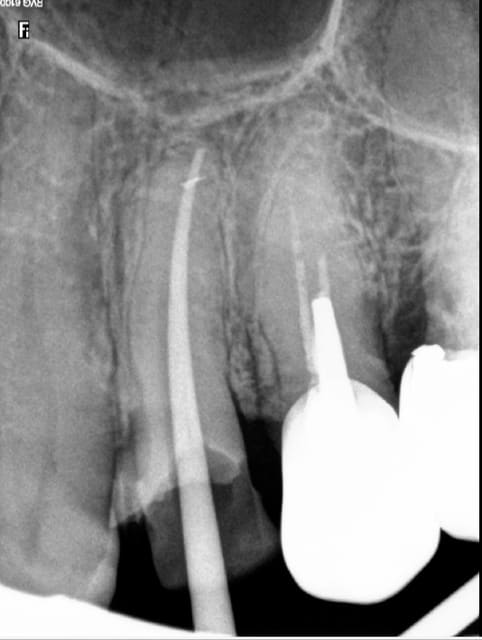

24/11/2015 à 15h36

L'instrument s'est cassé à la base donc il est entier quasiment dans le canal donc normalement pas trop difficile à retirer pour un spé mis impossible de passer à côté. Passons sur les raisons de cette fracture (cabinet nouveau, pas glyde, ouverture chambre pas satisfaisante ? Problème de l'instrument ? Problème de moi !?) vous semble-t-il honnête de demander à régler en 50/50 entre moi et le titulaire ou je pousse le bouchon un peu trop loin !!!

Capture d e cran 2015 11 24 23.14 - Eugenol

Tu dis rien en général, il ne se passe rien. C'est un aléa thérapeutique. Tu surveilles l'évolution éventuelle. Un apex en crochet par exemple ca arrive et à tout le monde endos exclusifs inclus ( moins peut etre parce qu'ils prennent leur temps et qu'ils font ca toute la journée)

Je paye une caisse de champagne à l'endo exclusif qui va me retirer ca par voie orthograde.-)))

Ca c'est à cause du localisateur d'apex, j'y étais mais ce con me disait que j'y étais pas tu insistes et paf. ( il a merdé sur l'autre canal d'ailleurs dépassement de 2 mm cone radio coupé de 2mm)

Capture d e cran 2015 11 25 13.18 - Eugenol